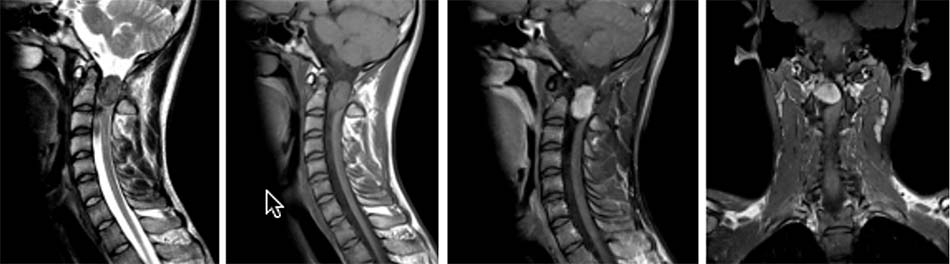

2.2. Tổn thương trật đội – trục do viêm khớp dạng thấp

Biểu hiện lâm sàng viêm khớp dạng thấp lần đầu tiên được mô tả vào năm 1800 bởi Landre – Bouvais tại bệnh viện Salpetrière, Paris. Năm 1859, Garrod đặt tên cho bệnh này và tới năm 1890 ông đã thông báo 36% bệnh nhân viêm khớp dạng thấp có tổn thương cột sống cổ. Waaler (năm 1940) và Rose (năm 1948) đã tìm ra yếu tố dạng thấp [32].

Trong quá trình tiến triển, 83% bệnh nhân có tổn thương khớp đội – trục bắt đầu vào năm thứ hai của bệnh. Tùy theo thời gian mắc bệnh, tần suất gặp tổn thương khớp đội – trục trên chẩn đoán hình ảnh cột sống cổ chiếm 43-86% [32].

Cơ chế của quá trình trật C1-C2 ra trước do quá trình ăn mòn bao hoạt dịch, xương và hệ thống dây chằng kết hợp với sức nặng của hộp sọ và các cử động khớp C1-C2. Tuy nhiên biểu hiện lâm sàng không rõ ràng, thường triệu chứng xuất hiện sau khoảng 10 năm hoặc hơn sau đó. Bất cứ một khớp hoạt dịch nào trong cơ thể đều có thể bị tổn thương, nhưng sự thay đổi sớm nhất lại xảy ra ở hệ thống khớp C1-C2 [15],[31],[33],[45],[53].

Weissmann và cộng sự nghiên cứu hồi cứu 194 bệnh nhân thấy rằng chèn ép tuỷ xuất hiện khi khoảng cách trật bên C1-C2 trượt ra trước khoảng 9 mm. Gần đây Boden và cộng sự nghiên cứu trên 73 bệnh nhân phát hiện ra kích thước còn lại của tuỷ sống nếu còn 14 mm hoặc nhỏ hơn sẽ xuất hiện các thương tổn thần kinh. Sự tổn thương đứt gãy của dây chằng ngang cũng là nguyên nhân gây trượt C1-C2 [45].

Pellicci và cộng sự nghiên cứu trong 5 năm với 106 bệnh nhân viêm khớp dạng thấp cho thấy 80% bệnh nhân này có tổn thương trên Xquang khớp C1-C2 với hình ảnh thoái hoá rõ ràng, sau 5 năm 36% có tiến triển nặng lên và xuất hiện tổn thương về thần kinh. Marks và Sharp mô tả 31 bệnh nhân có tổn thương trật C1-C2 có hẹp ống sống cổ, 50 % chết trong vòng 6 tháng và đều nằm trong nhóm không được điều trị gì [32].

Một nghiên cứu khác trên 104 bệnh nhân cho thấy có 11 bệnh nhân trong số này là tổn thương trật C1-C2 và có chèn ép tuỷ, 7/11 trường hợp này chết đột tử, nghiên cứu cho thấy trật C1-C2 có chèn ép tuỷ chiếm khoảng 10%.